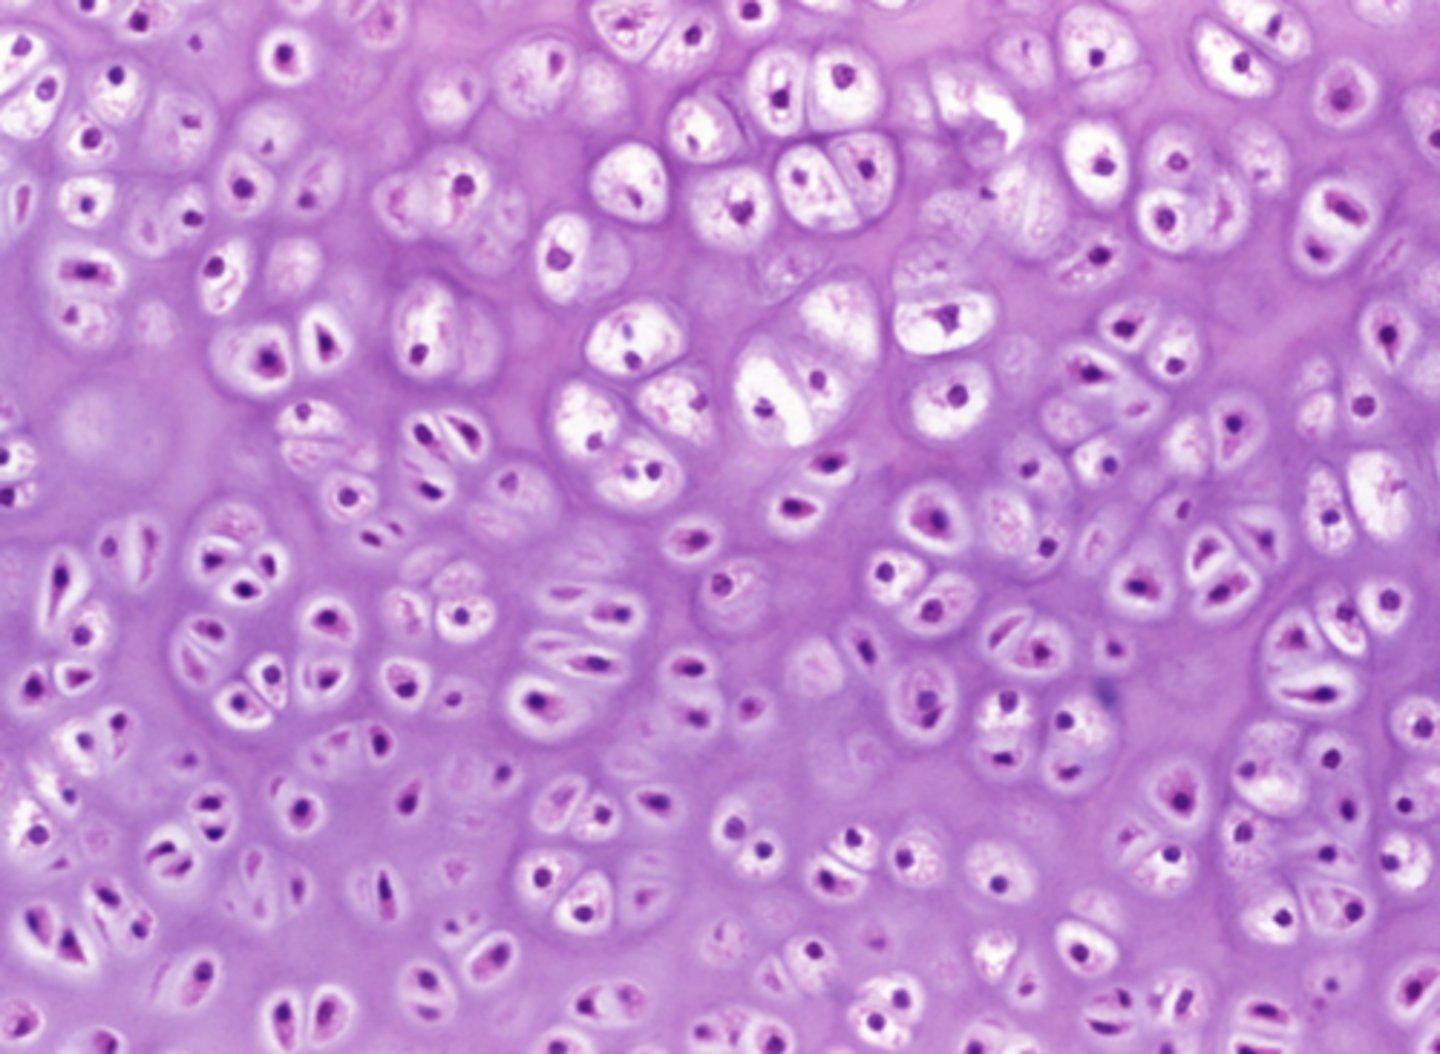

Which of the four major tissue types is presented in the following image of the distal femur:

Flexible extracellular matrix with no blood or nerve supply

Which feature in the previous image is responsible for cushioning the body from mechanical impact?

Flexible extracellular matrix with no blood or nerve supply

Basement membrane supporting the cells' basolateral surface

Rigid extracellular matrix rich in calcium

Densely packed actin and myosin filaments